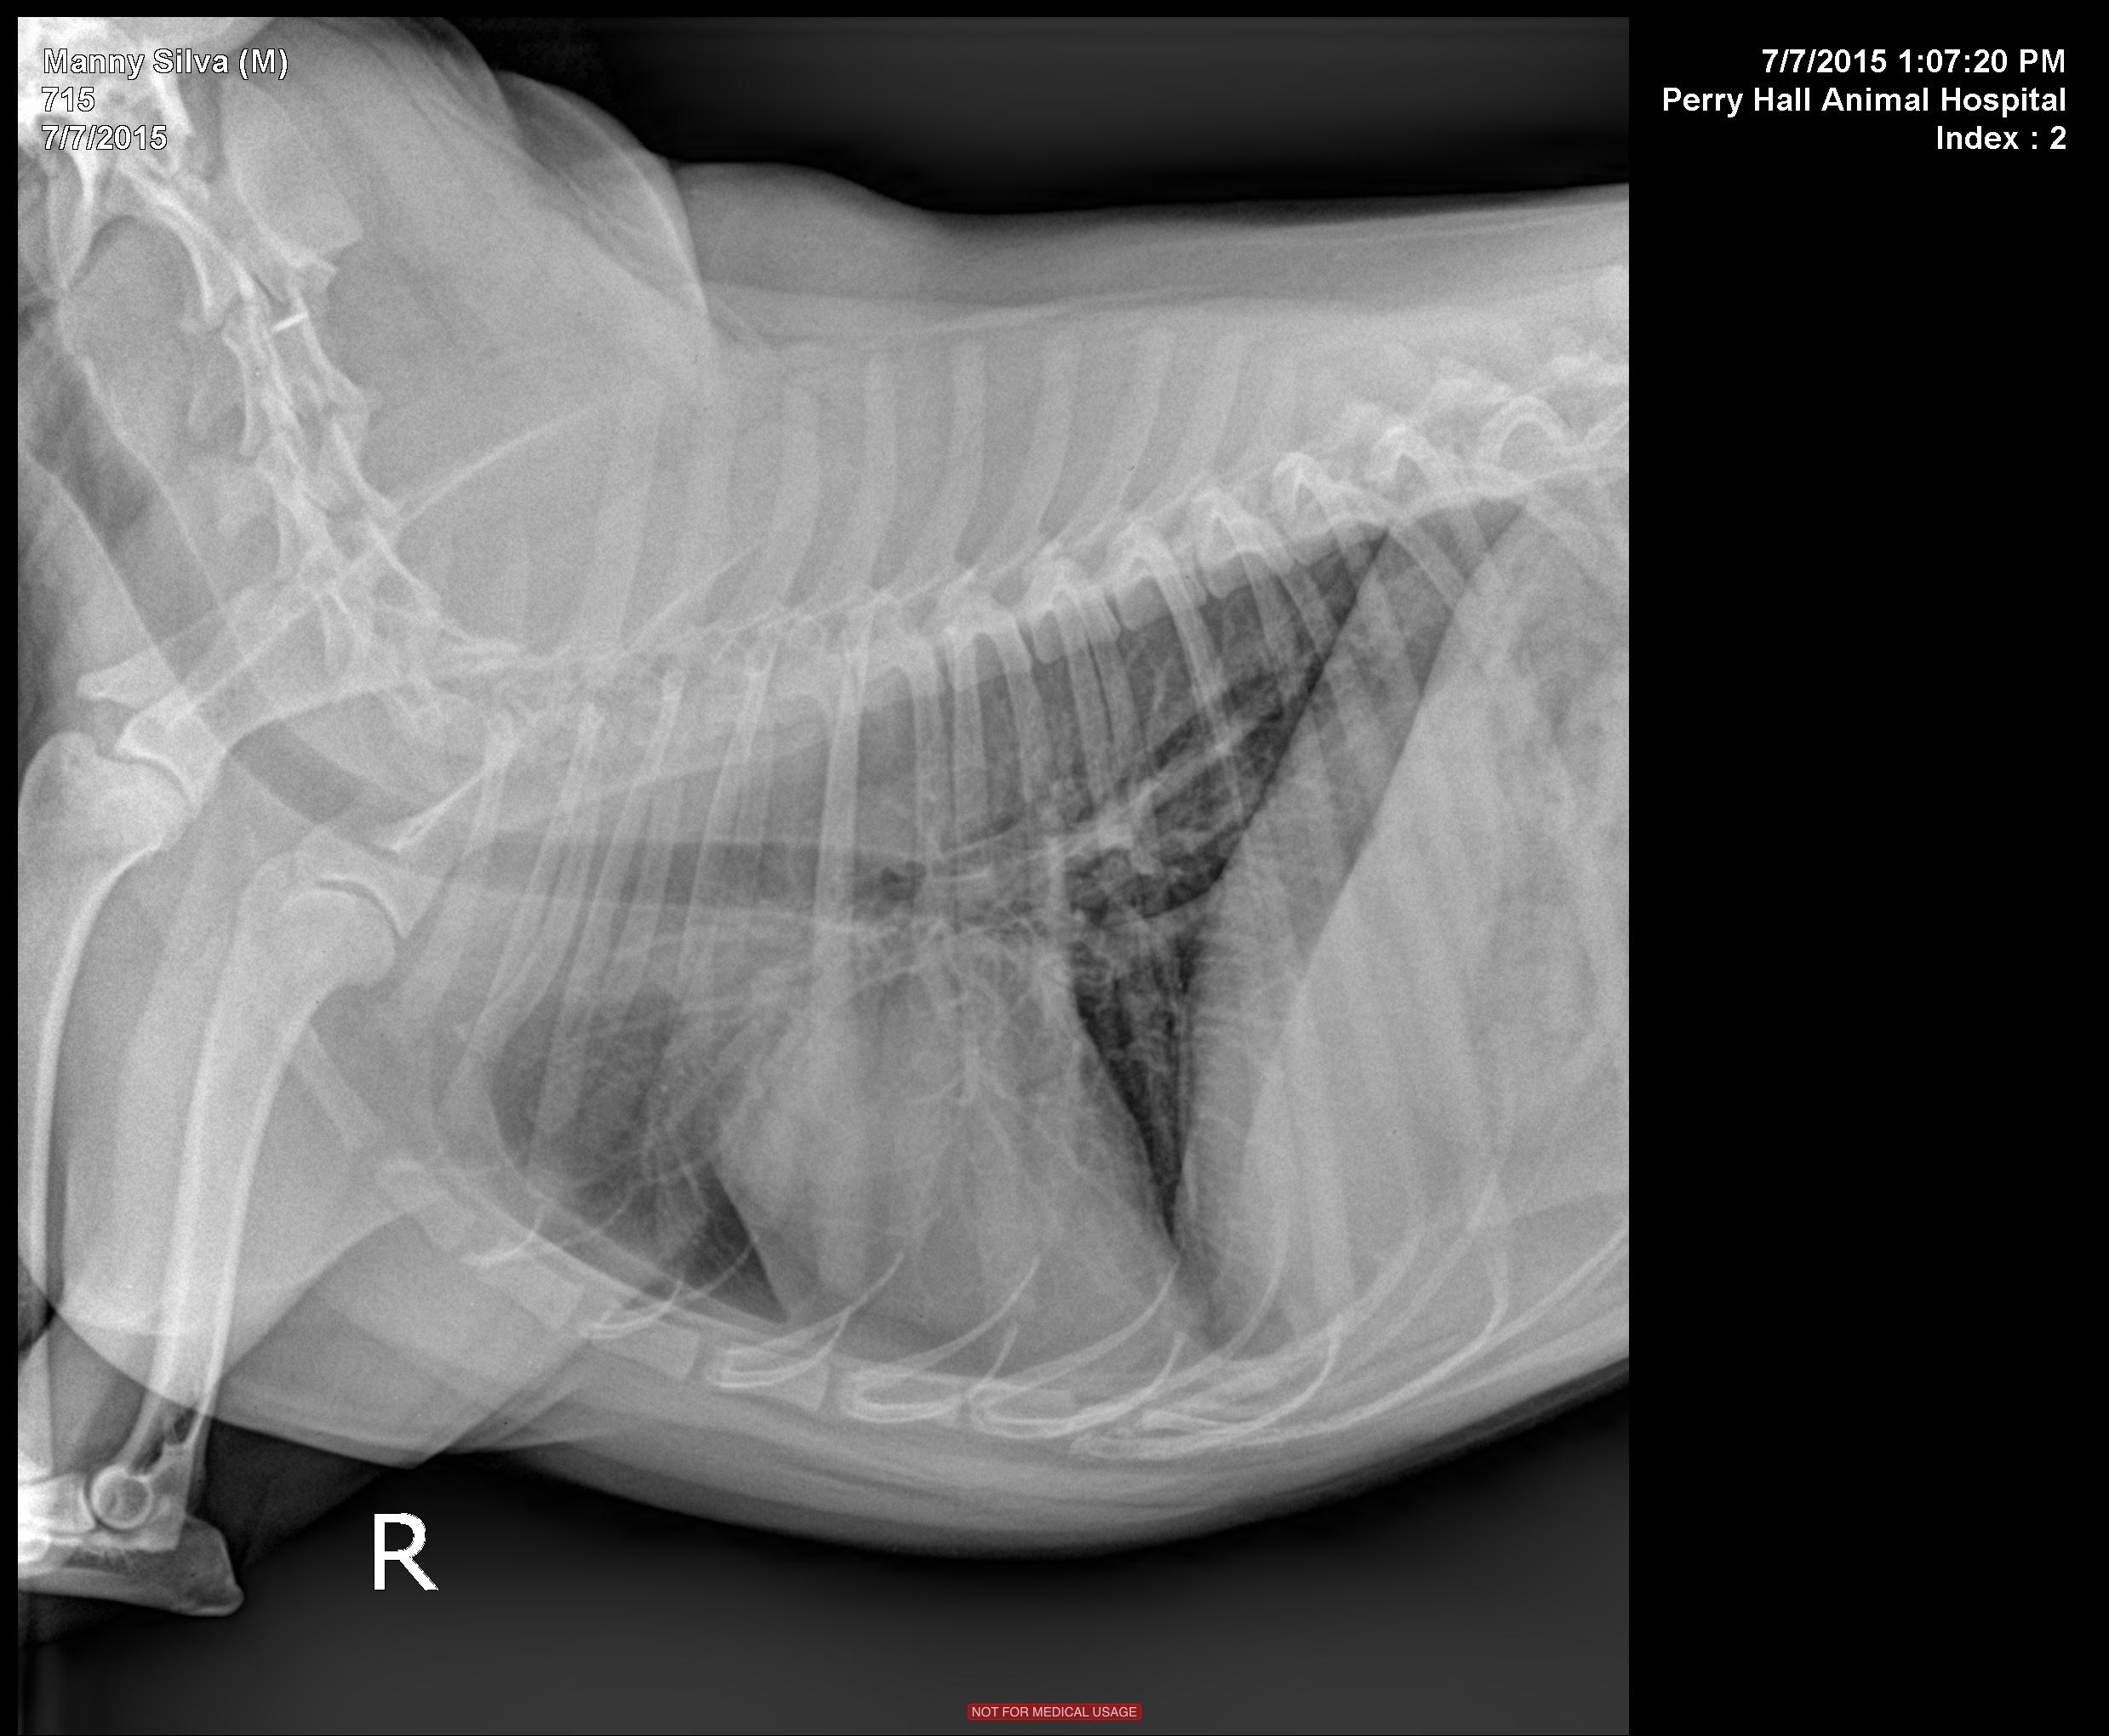

History of 3 recent episodes of hairball-type cough/wheeze/gag. Physical exam showed all WNL; no coughing episodes during the exam or during the stress of radiographs. CBC and chemistry panel pending at this time.